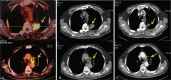

Diagnosis: Needle biopsy and positron emitted tomography/computed tomography were performed. The patient was diagnosed with advanced NSCLC adenocarcinoma with bone and lymphatic metastasis. Next-generation sequencing of circulating tumor DNA was performed, which identified a p.A289V mutation in the EGFR gene of the patient.

Outcomes: Our patient had a partial response to Icotinib after treatment for 5 months during the therapeutic trial by TKIs. The patient showed adverse symptoms of mild diarrhea and rash (Common Terminology Criteria for Adverse Events grade 1) during the treatment.